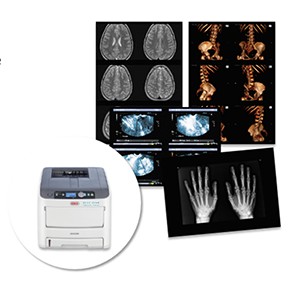

Лазерная камера для печати медицинских изображений на пленке стандарт dicom